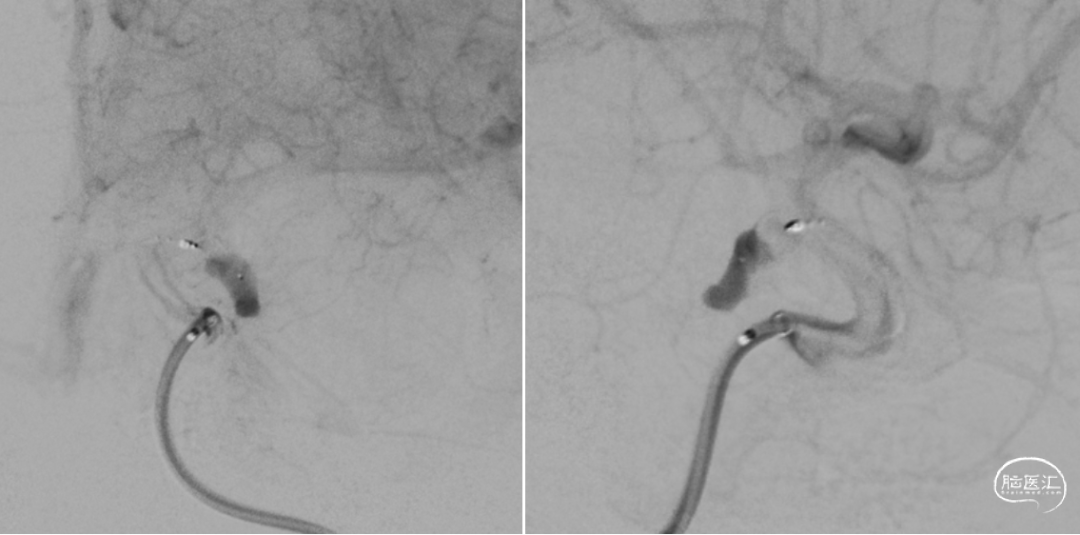

微导管3D评估动脉瘤与载瘤动脉关系

微导丝支撑和保护下WEB释放

近端瘤颈残留,web按摩贴壁

按摩后瘤颈近端内漏消失!

前

后